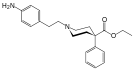

4-Phenylpiperidines

Prodines

- Allylprodine

Structures